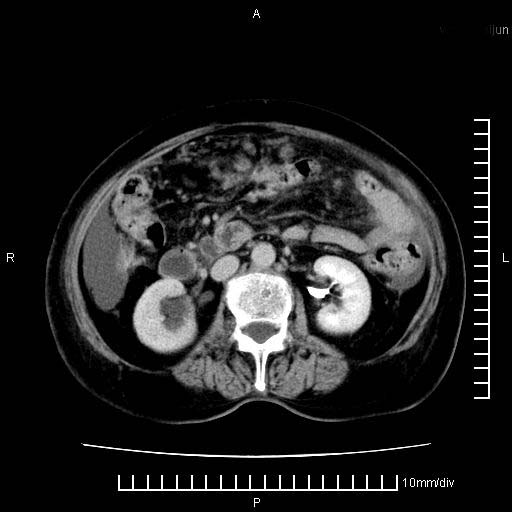

标题: CT28280:腹部增强:女性,80岁

上腹疼痛月余,外院核磁诊断胰腺癌。现临床示右下腹可明显触及包块,可片子上怎么没有看到?

1.胰腺颈体部癌。

2。腹腔积液。

3。右胸腔积液,伴右肺下叶部分萎陷。

4。右肾盂囊肿。

胰腺结构模糊,胰尾部见囊性包块,周围脂肪密度增高,左肾前筋膜增厚,胸水、腹水。不符合胰腺ca伴腹膜腔转移。考虑胰腺炎伴假性囊肿形成、胸腹腔积液。

右肾盂囊肿。

1)考虑胰腺癌并胰腺假性囊肿形成。2)肝内低密度灶,不排除转移。3)右肾盂积水。4)腹水。5)右侧胸腔积液并右肺下叶部分膨胀不全。